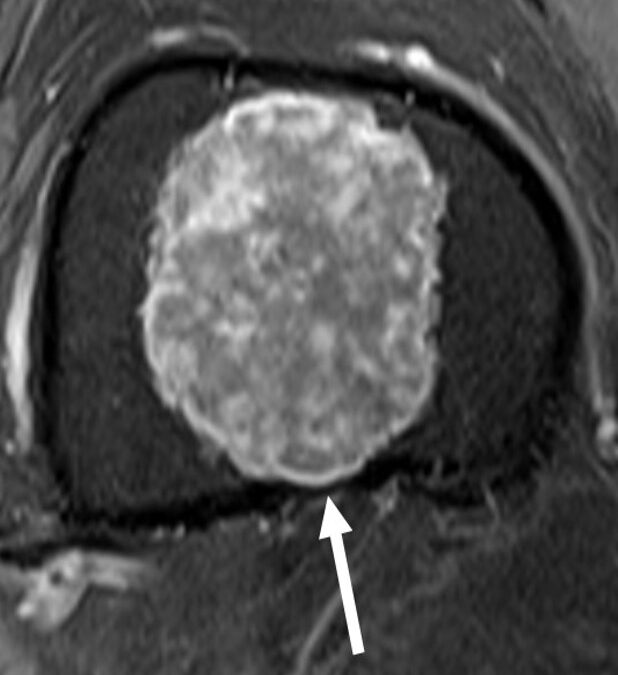

It is critical to determine if a lesion is benign or malignant. However, it is especially difficult in the case of grade 1 chondrosarcoma, even for a pathologist. This article focuses on the role of MRI in the differentiation of enchondromas from chondrosarcomas.

Article: What are the differentiating clinical and MRI-features of enchondromas from low-grade chondrosarcomas?